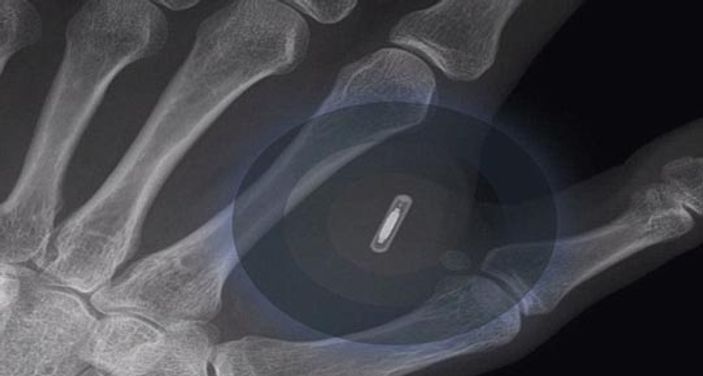

Avustralya’nın Brisbane kentinde yaşayan Ben Slater, eline taktırdığı mikroçip sayesinde elinin bir hareketiyle kapıları ve ışıkları açıp kapatmayı başardı. Slater, bir dövmecide eline yerleştirilen pirinç tanesi büyüklüğündeki mikroçip sayesinde, yeni iPhone 6 ile de ‘ iletişim kurmayı’ hedefliyor.

Tüm dünyada merakla beklenen iPhone 6, Apple tarafından yarın piyasaya sürülecek. Reklam direktörü Slater, Daily Mail Avustralya’ya, geleceğin teknolojilerinin daima ilgisini çektiğini söyledi. Slater, Apple’ın yeni akıllı telefonunun elinde yerleştirdiği çipi de okuyabileceğini düşünüyor. İnsana mikroçip uygulaması Avustralya için yeni olsa da ABD’de 2004 yılından beri hızla yaygınlaşıyor. Mikroçiplerde kronik hastalığı olan kişilerin sağlık bilgileri tutuluyor.